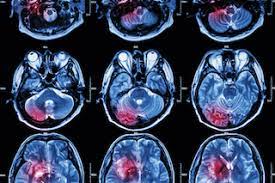

Are Brain Cancers On The Rise : What Is Glioblastoma Symptoms Causes Diagnosis Treatment And Prevention Everyday Health / Soft tissue cancers, like those that develop.. In general, brain tumors are more common among older people, but statistics even show an increase in brain tumors in kids. The cancer cells break away from the primary tumor and travel to the brain, usually through the bloodstream, then commonly go to the part of the brain called the cerebral hemispheres or to the cerebellum. And now experts say the incidence of brain cancer may be on the rise. Treating brain tumors takes a team of. The average annual increase was 1.37 %.

A new study has revealed that 10 years of cellphone use resulted in an average 290% increased risk of brain tumor development. And now experts say the incidence of brain cancer may be on the rise. In general, brain tumors are more common among older people, but statistics even show an increase in brain tumors in kids. Metastatic tumors are considered cancer and are malignant. New studies of epidemiological data from this country and abroad indicate that the rise is especially dramatic among the.

Leukemia is the most common cancer in kids. The cancer cells break away from the primary tumor and travel to the brain, usually through the bloodstream, then commonly go to the part of the brain called the cerebral hemispheres or to the cerebellum. The incidence increased by 35 percent in children younger than 15, according to the website pediatric oncology education materials, which provides information for healthcare professionals. Nearly 78,000 new cases of primary brain tumors are expected to be diagnosed this year. Metastatic tumors to the brain affect nearly one in four patients with cancer, or an estimated 150,000 people a year. By jillian mock sep 18, 2020 11:45 am (credit: Brain tumors can be malignant (cancerous) or benign (not cancerous). The average annual increase was 1.37 %.

Some genes control when our cells grow, divide into new. The standard treatments for brain tumors include surgery, radiation and chemotherapy. (cnn)the incidence rate of aggressive malignant brain tumors in england has more than doubled in recent decades, and a new study questions what could be driving that rise. Unlike cancers that start in other parts of the body, tumors that start in the brain or spinal cord rarely spread to distant organs. Metastatic tumors to the brain affect nearly one in four patients with cancer, or an estimated 150,000 people a year. The cancer cells break away from the primary tumor and travel to the brain, usually through the bloodstream, then commonly go to the part of the brain called the cerebral hemispheres or to the cerebellum. What you need to know. Soft tissue cancers, like those that develop. Some of the cancers that are on the rise are preventable. We found that the incidence rate of all pediatric brain tumors has been on a gradual but steady increase from 1973 to 2008 (p < 0.001). A new study has revealed that 10 years of cellphone use resulted in an average 290% increased risk of brain tumor development. Cancer is on the rise among young people over the past decade, cancers associated with obesity show some of the most troubling increases affecting young adults and adolescents. Dna is the chemical that makes up our genes, which control how our cells function.